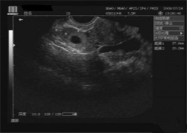

現(xiàn)代的婦科B超檢查有兩種方式:腹部和經(jīng)陰道腔內(nèi)的B超。

陰式B超(陰超)是一種腔內(nèi)超聲,是將超聲探頭直接放在陰道內(nèi)進(jìn)行超聲檢查的一種方法,而陰式B超(陰超)不需要憋尿,探頭在陰道內(nèi)緊貼宮頸及后穹窿不像腹部B超,聲束要經(jīng)過腹部皮膚、肌肉,所以盆腔顯示更加清晰。尤其是對后位子宮、子宮內(nèi)膜癌、子宮肌瘤、前置胎盤等的觀察,圖像顯示比腹部超聲明顯清晰。(無性生活的女性朋友需提前告知醫(yī)師,此項檢查禁止操作)。